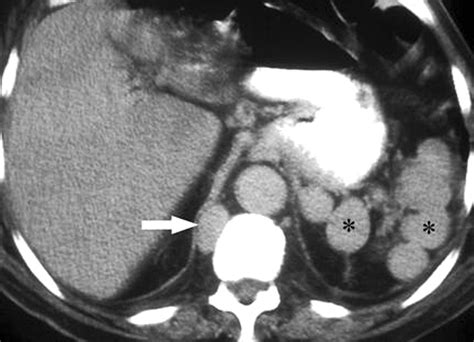

• Computed Tomography (CT) Scan: CT scans provide detailed images of the diaphragm and surrounding structures, aiding in the diagnosis of complex conditions.